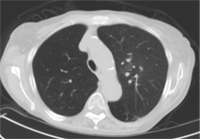

Before

Early stage lung cancer prior to therapy (red arrow).